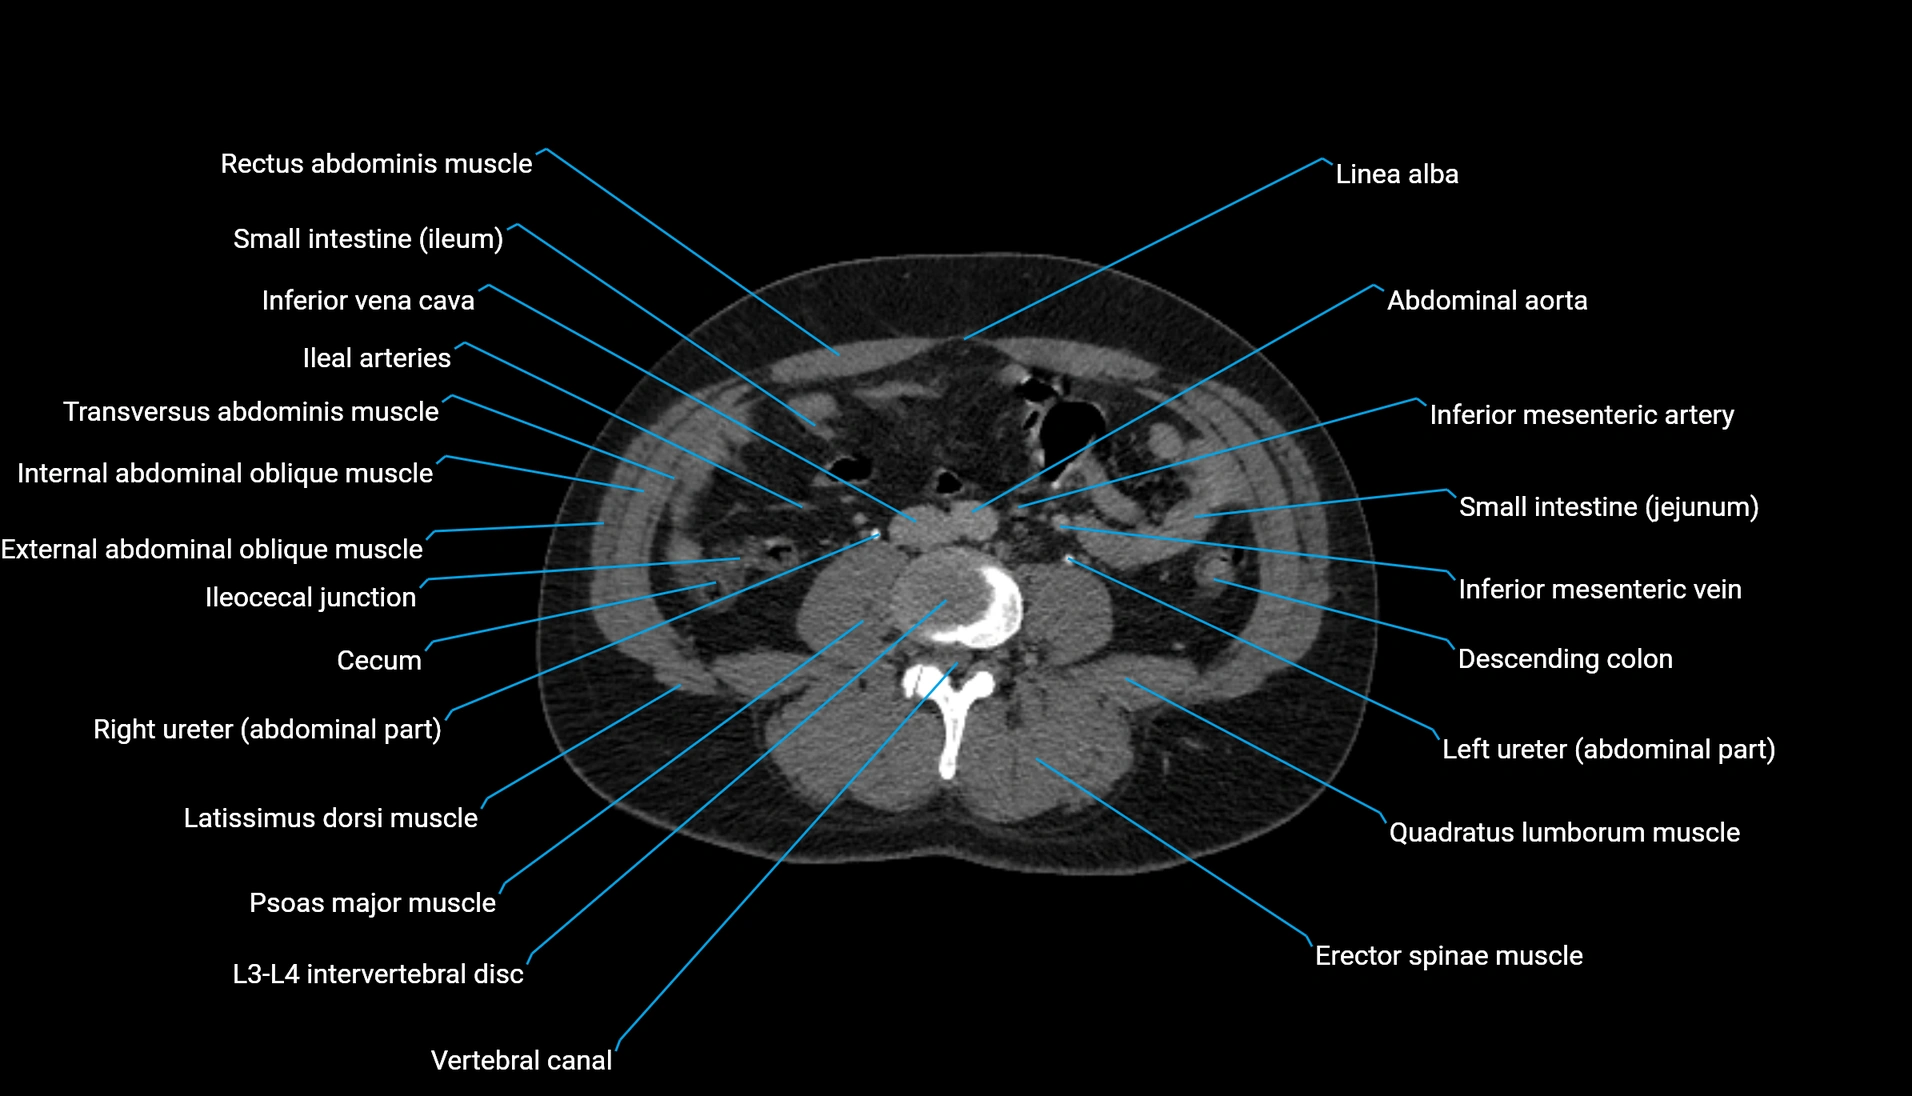

CT Appearance

Non-contrast CT:

-

Demonstrates cortical bone of acetabular rim in excellent detail

Detects fractures, dysplasia, retroversion, or bony overcoverage (pincer impingement)

3D reconstructions used in preoperative hip surgery planning

CT VRT 3D image

CT image